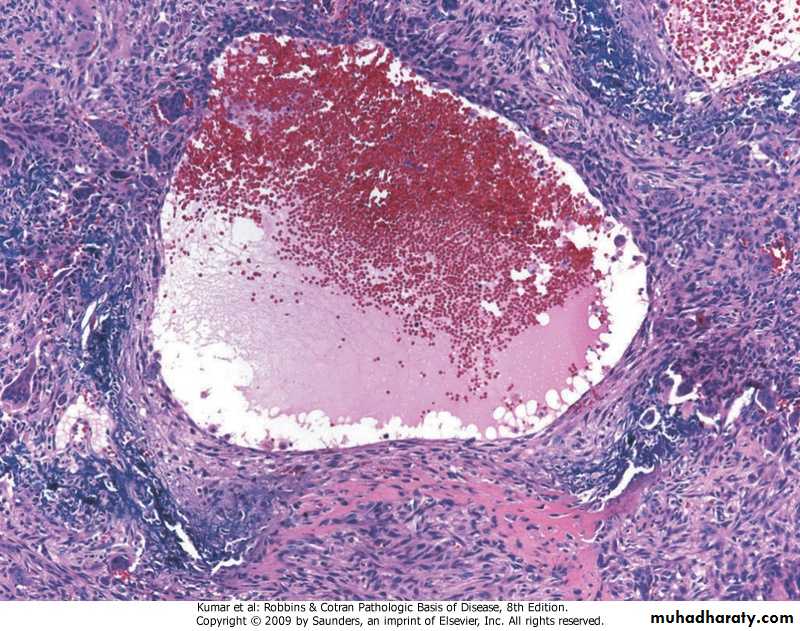

Aneurysmal bone cyst with blood-filled cystic space surrounded by a fibrous wall containing proliferating fibroblasts, reactive woven bone, and osteoclast-type giant cells